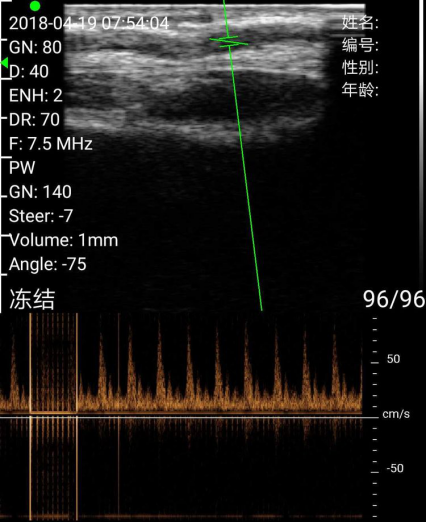

测量尺动脉流速(这个功能很给力)